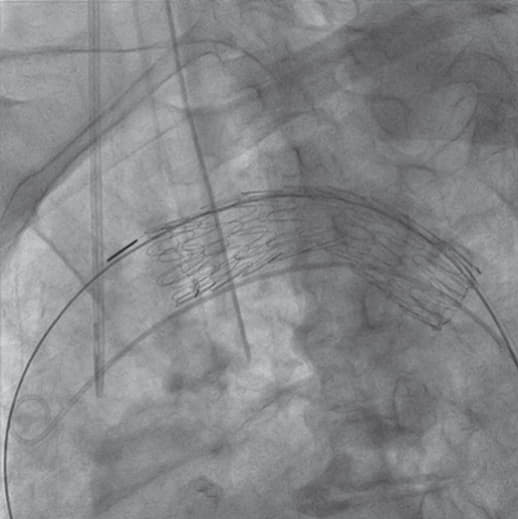

右総大腿動脈に6 Frシースを留置し、アクセスとした 。ラジフォーカスTMガイドワイヤーM**および 5 Frピッグテールカテーテルを上行大動脈まで進行させ、manipulateしたEgoist® EGU35-AC300Q (Arch Curve)ガイドワイヤーを大動脈基部まで到達させた。この時点で透視下にガイドワイヤー押し付けを行い、安定した状態で大弯側に押し付け可能なこと、左室内へ迷入しないことを確認した。22 Frゴア®ドライシール フレックス イントロデューサシースを進行させ、引き続きTAG® コンフォーマブル ステントグラフトTGMR373710Jを適正位置まで進行させた。DSAを施行し、左総頚動脈(LCCA)および左鎖骨下動脈(LSCA)の位置を確認した。ここからは、術者(ドライシールシース固定およびデリバリーカテーテルの操作)・助手(デリバリーカテーテルの固定、ガイドワイヤーの押し付け)の共同操作にて一次・完全展開を行った。ガイドワイヤーを軽く押し付けた状態で、パーシャルアンカバーステントがLCCAに若干かかる位置で一次展開を施行した。ガイドワイヤーの押し付けを加えて、LCCA直下にパーシャルアンカバーステントが位置するように微調整を行った。DSA上のZone 2レベルの小弯側に合わせて、アンギュレーションコントロールダイヤルを回転させて至適な角度に調整した。ガイドワイヤーを押し付けた状態で完全展開を施行した。DSAを施行し、コアキシャルに留置されていること、特に小弯側が至適角度で留置されていることを確認し、この時点でのアンギュレーションコントロールは必要ないと判断した。ガイドワイヤーを用いて、慎重にピッグテールカテーテルを抜去し、引き続き完全展開を施行した。DSAを施行し、エンドリークが無いことを確認した。左上腕動脈よりアクセスし、LSCA根部で造影した。DSA上、明らかなType ll エンドリークを認めず、deployment sleeve部分を含むステントグラフトにてLSCA根部が完全に被覆・閉鎖されていることが確認できた。